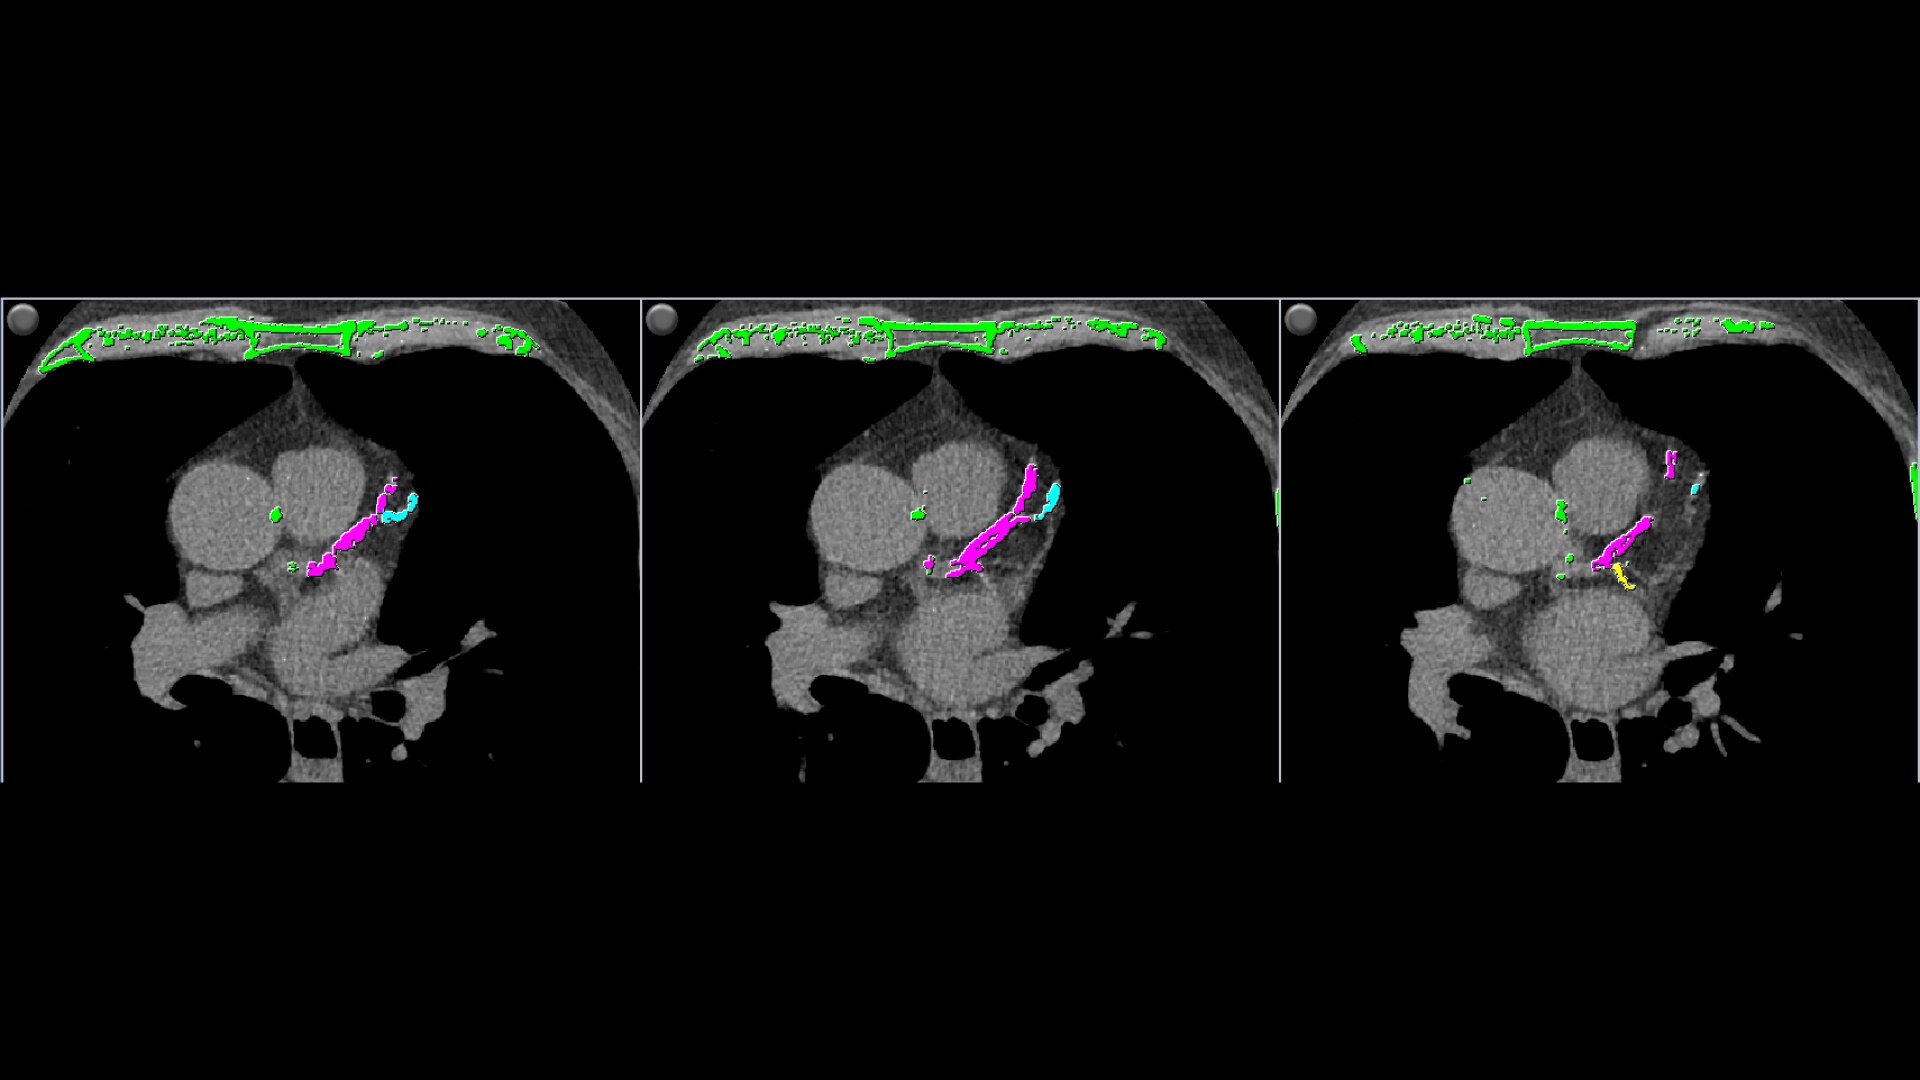

Single-click calcium labeling.

• Automatically detects calcium and highlights it in green

• Individual and aggregate scores are computed for each artery type